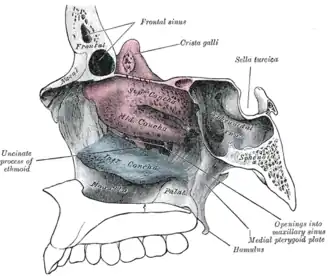

Base do crânio. Superfície superior. Parede medial da fossa nasal esquerda.

Parede medial da fossa nasal esquerda. Paredes da cavidade nasal esquerda.

Paredes da cavidade nasal esquerda. Parede lateral da cavidade nasal.

Parede lateral da cavidade nasal.